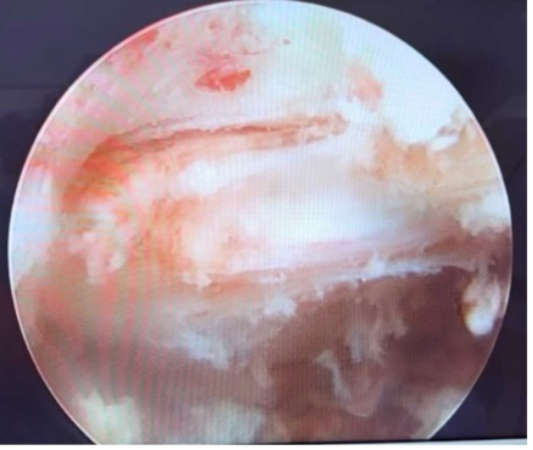

时间不等人,为赢得宝贵的救治时间,骨科团队决定立即在急诊局部麻醉下行椎间孔镜下脊髓减压及病灶活检术。「这是一个『一石二鸟』的策略。」主刀医生郑琦主任解释,「在局麻下进行微创孔镜手术,创伤小、风险可控。既能迅速解除脊髓最紧迫的压迫,为神经功能恢复争取『黄金时间』,又能精准获取病变组织,送病理检查以明确病因。」

手术顺利完成。

术后第一天,令人振奋的迹象出现:王女士的双下肢肌力恢复至 1 级。更关键的是,分子生物学结果很快明确诊断为「结核分枝杆菌感染」。第一步,精准诊断与紧急减压,成功完成!